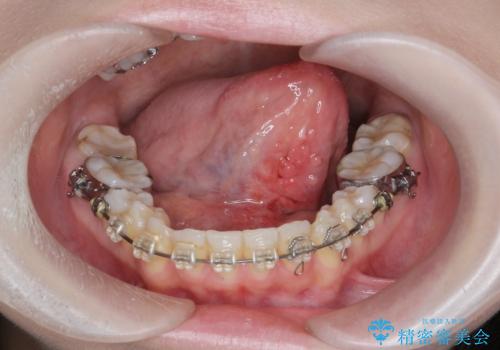

- 「歯がぐらぐらして噛めない。」、全体的な治療を希望されて来院されました。

クラウン・コアを除去したところ支台となる歯は破折し残すことが難しい状況でした。

インプラント治療を行ったことでしっかりとした咬合関係を確立することができました。